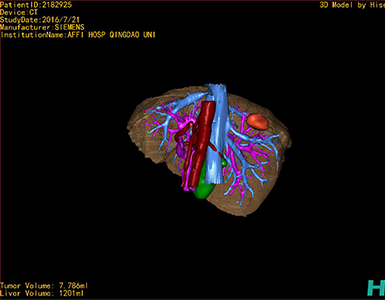

将0.625mm双源薄层CT资料的静脉期和动脉期Dicom格式文件导入海信CAS系统。

通过调节窗宽窗位调整CT序号,对肿瘤,肝实质,胆囊,下腔静脉,肿瘤,肝动脉、门静脉及肝静脉等进行三维重建;系统自动计算肿瘤体积和肝脏体积。

模拟手术操作,自动计算切除肿瘤体积。肝脏体积为1201ml,肿瘤体积为7.786ml,肿瘤体积为肝脏体积的0.6%,通过比对40-50岁正常肝脏体积为1368.38±279.24 ml,肝脏可先进行保守治疗,肾脏进行部分切除术。

术前手术方案的规划。

术前三维重建:

重建图片